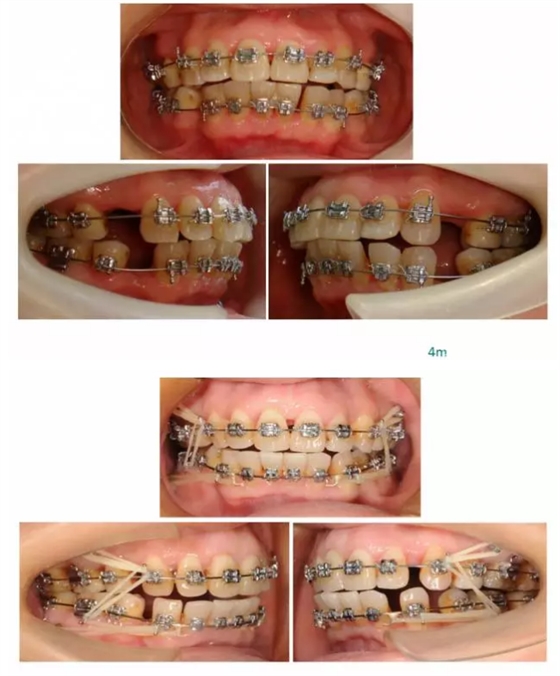

【原創(chuàng)博客】這樣的代償矯治大家滿意嗎?(重度骨性二類)——侯志明